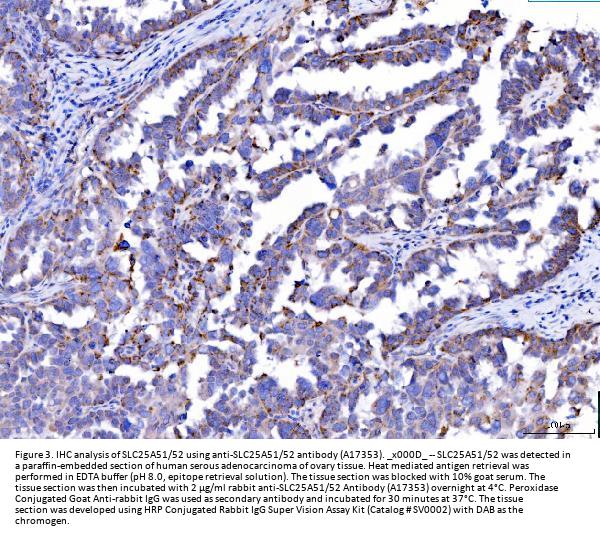

Immunohistochemistry(Paraffin-embedded Section), 2-5 μg/ml, Human

Boster Bio Anti-SLC25A51/52 Antibody Picoband® catalog # A17353. Tested in ELISA, Flow Cytometry, IF, IHC, ICC, WB applications. This antibody reacts with Human, Monkey, Mouse. The brand Picoband indicates this is a premium antibody that guarantees superior quality, high affinity, and strong signals with minimal background in Western blot applications. Only our best-performing antibodies are designated as Picoband, ensuring unmatched performance.